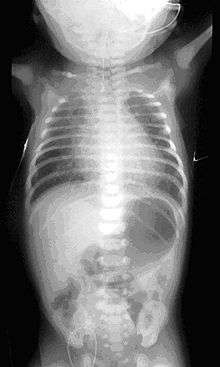

Common anatomical types of esophageal atresia a) Esophageal atresia with distal tracheoesophageal fistula (86%), Gross C. b) Isolated esophageal atresia without tracheoesophageal fistula (7%), Gross A. c) H-type tracheoesophageal fistula (4%), Gross E.[1] | |